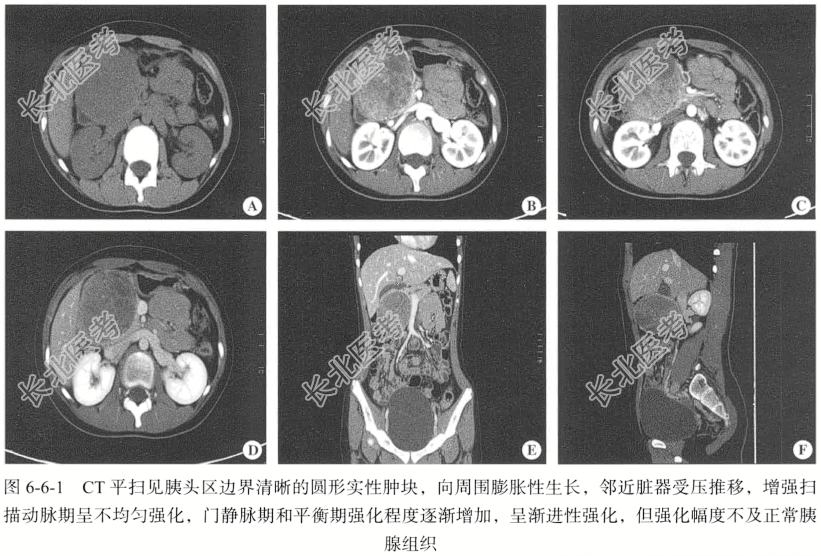

- [材料题] 【临床病史】女性,13岁,发现右上腹包块2月余。

【专科查体】右上腹可触及一包块,大小约6cm×6cm,质韧,活动性差,有压痛。

【腹部CT检查】仰卧位,横断位扫描,扫描范围自肝顶至盆底,CT扫描采用美国GE Discovery 750HD能谱CT扫描仪。层厚设定为5.00mm,层间距设定为5.00mm,重建间隔设定为2.50~5.00mm,螺距设定为0.50~1.50,最大管电压均为120kV,最大管点电流均设定区间在200~260mA。增强扫描对比剂采用碘伏醇(含碘320mg/ml),以3.5ml/s的流率注射1.5ml/kg,注射完成后以相同流率注射20ml生理盐水。分别延迟20~25秒,45~55秒行动脉期、门静脉期扫描。

【影像图片】见图6-6-1。

【手术所见】十二指肠中段、胰头部见一类圆形肿瘤,约为8cm×8cm。

【病理所见】结合HE形态学及免疫表型结果,符合胰腺实性假乳头状肿瘤(图6-6-2),肿物大小约为7cm×6cm×4cm,肿物位于十二指肠下方胰腺内,两侧肠切缘未见肿瘤累及,周围淋巴结未见肿瘤转移(0/1)。免疫组化结果:AE1/AE3(-),CD68(少+),CAM5.2(-),CK8(+),CD10(+),Vim(+),β-catenin(+),Syn(-),CgA(-),CD56(+),Ki-67(+8%),S-100(-),SMA(-),CD34(血管+)。

【病理诊断】胰腺实性假乳头状瘤。